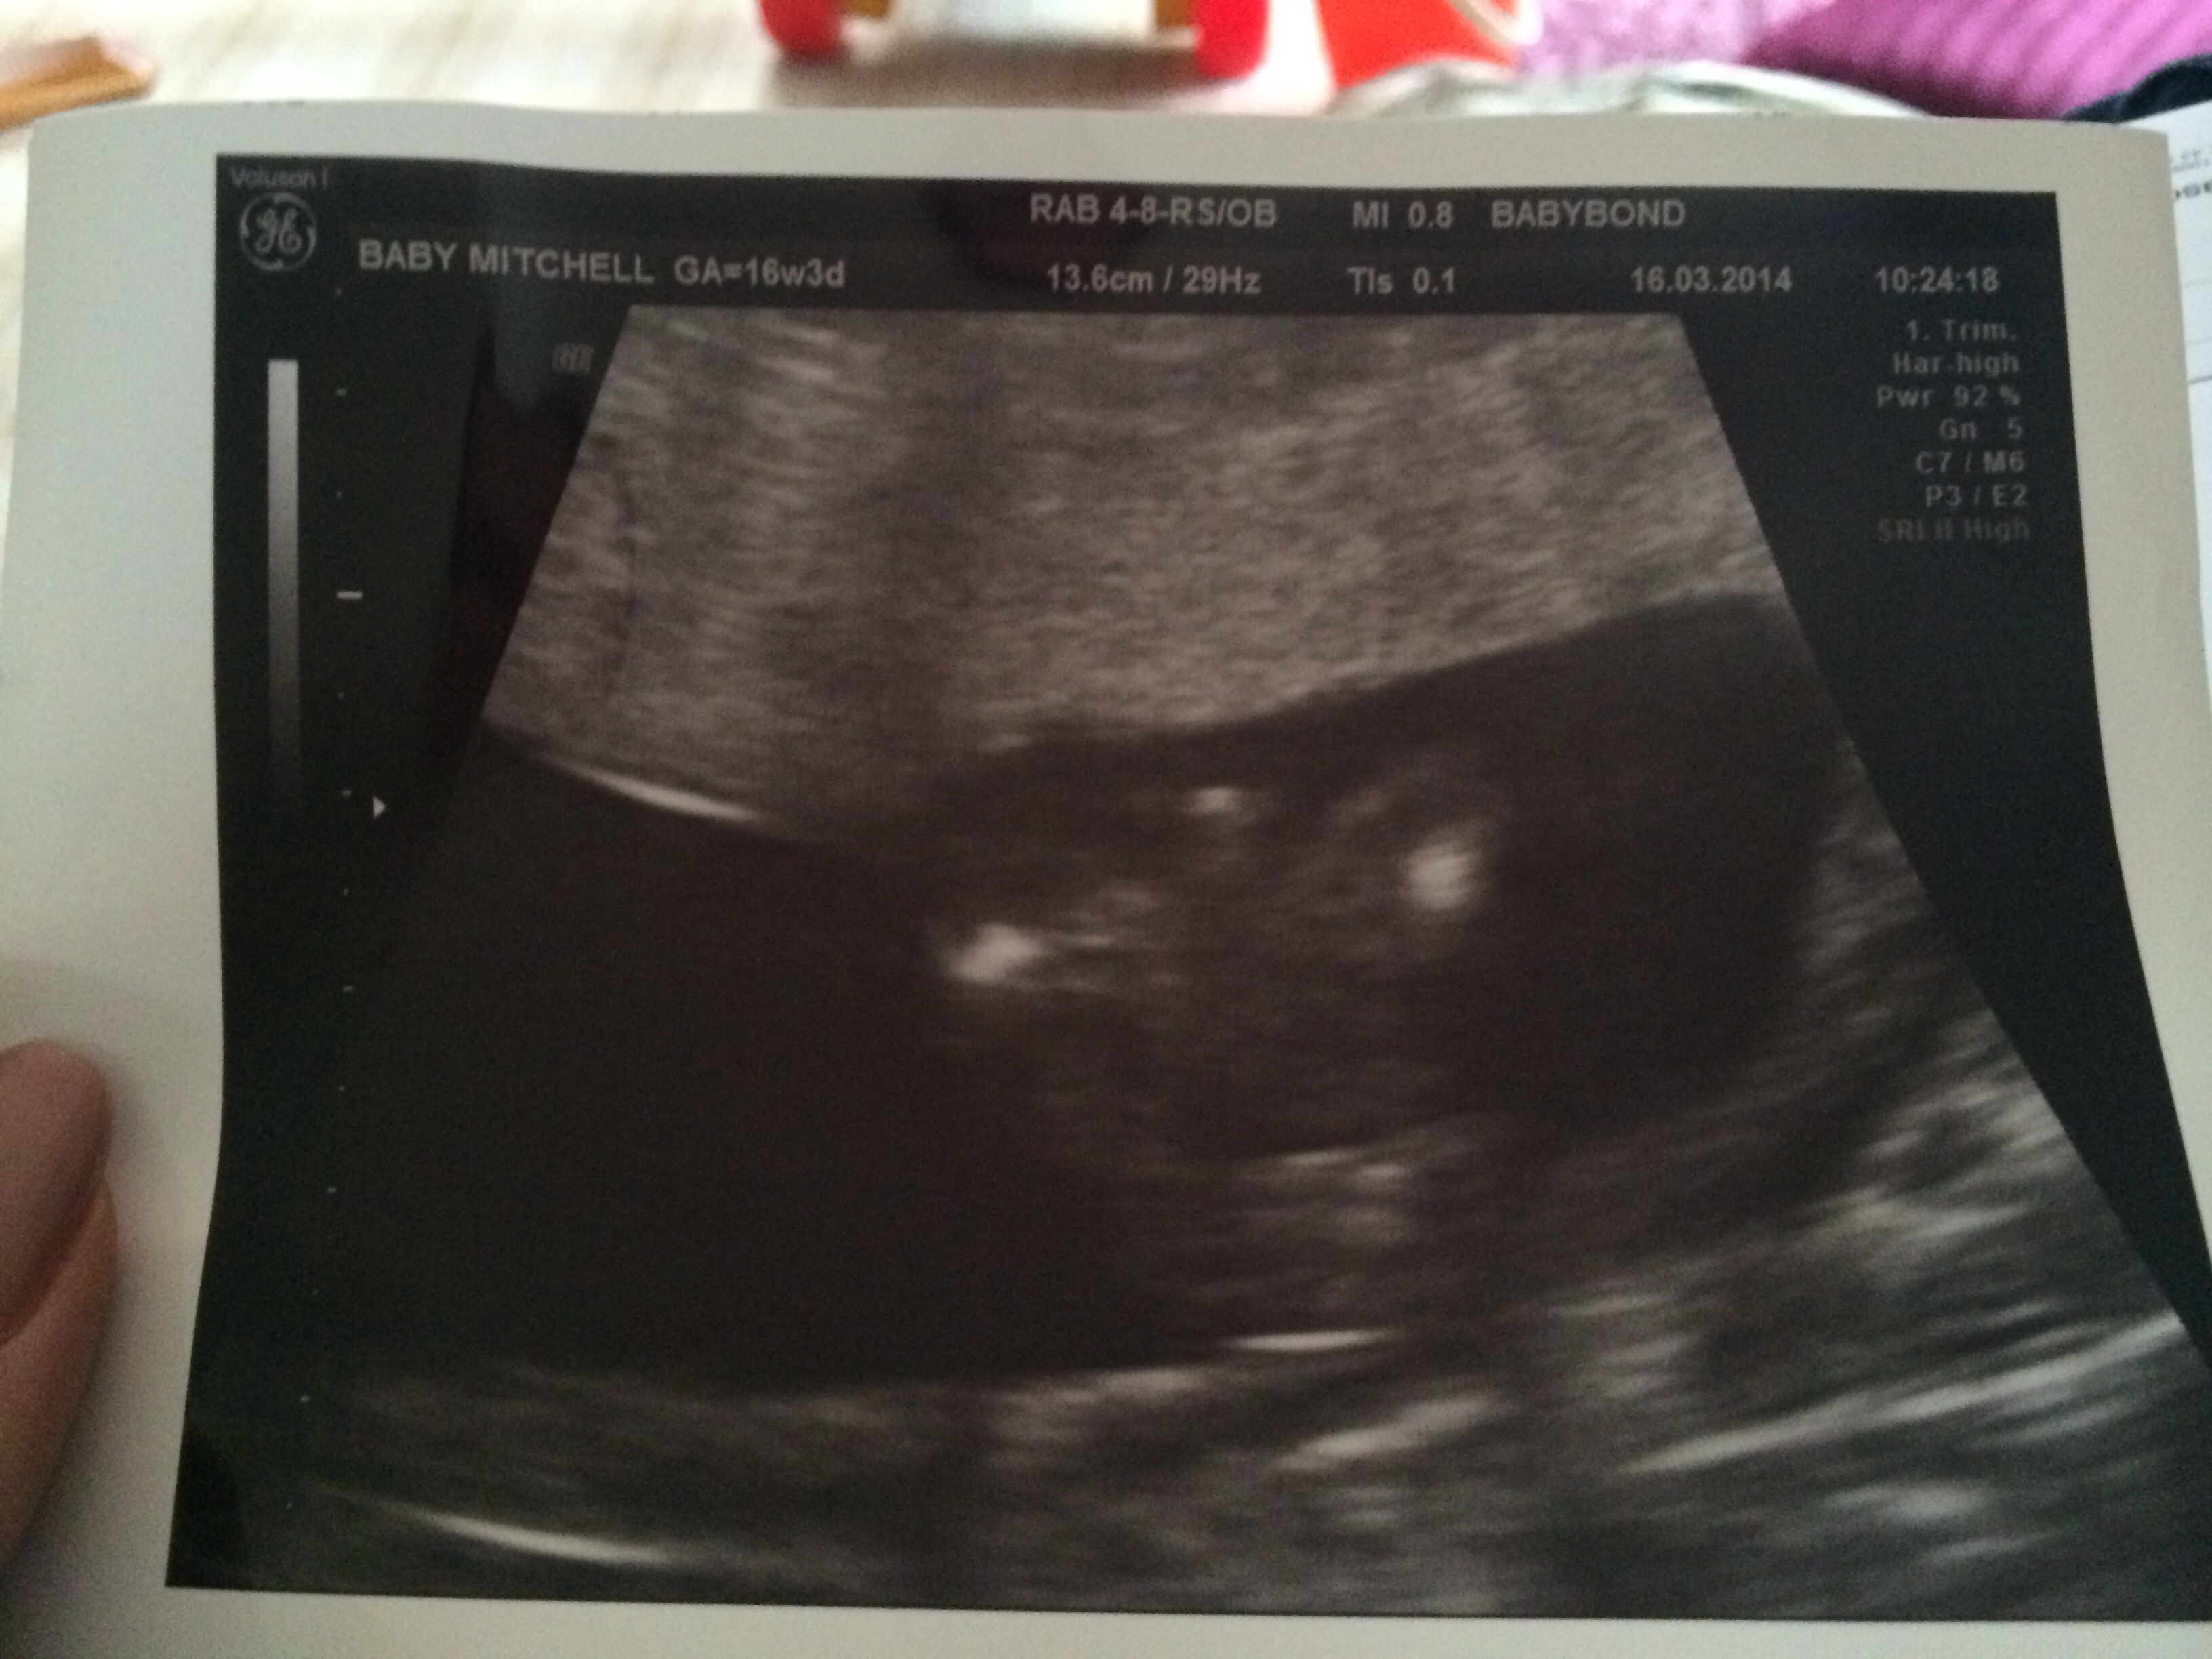

Scan at 16 weeks Attachment 17962

Attachment 17963

That's supposed to be the potty shot. They said boy.

Yup definitely boy :) congratulations!! Xx

If on the second picture the bottom is down and legs widespread (not an easy picture to see!), that's definitely a little man. Congrats! x